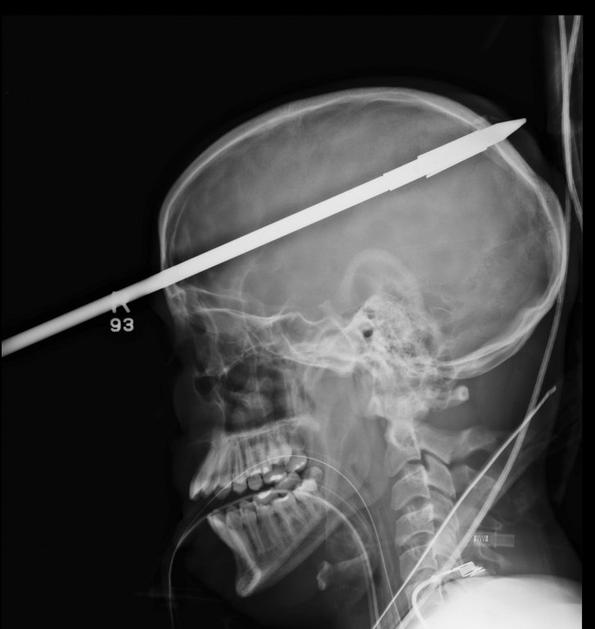

Glavo mu je preluknjala harpuna